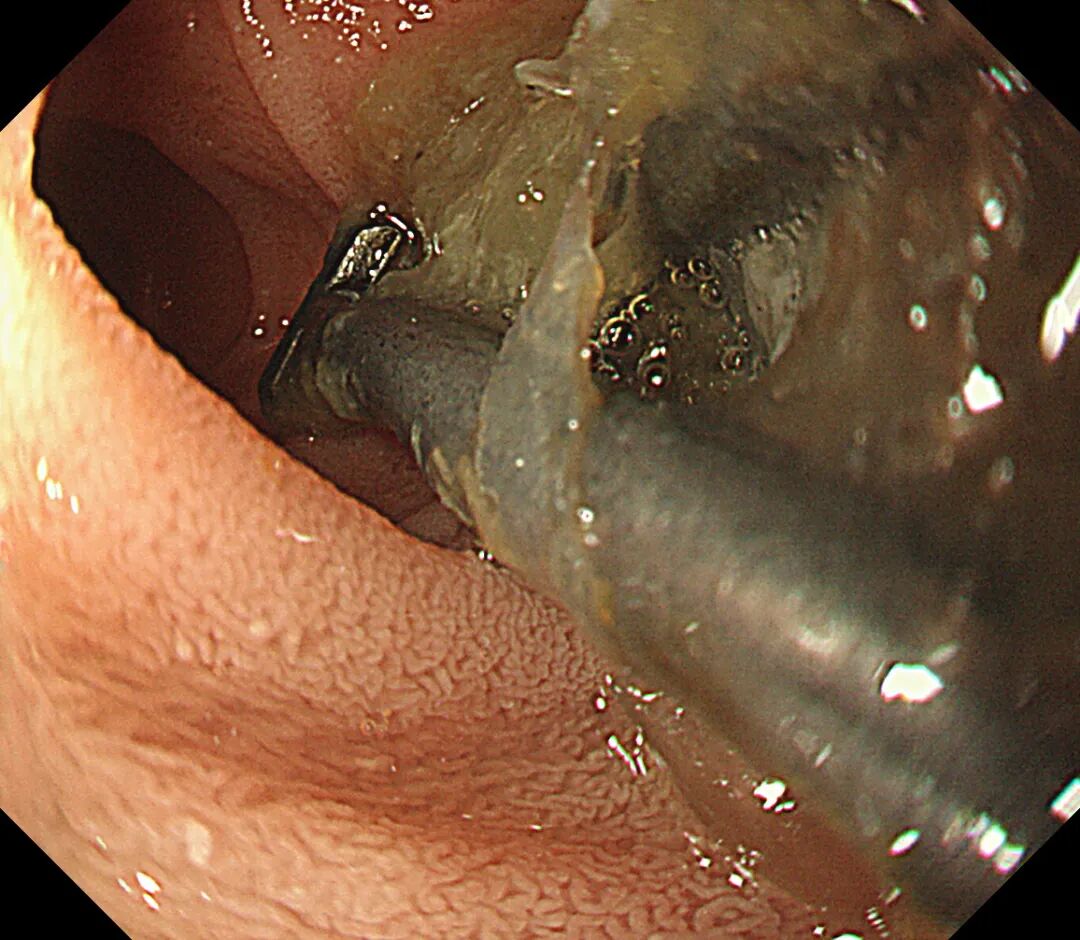

正当大家觉得松了一口气时,胃镜再次进镜复查,在十二指肠降段处又发现5枚铁钉,此处是胃镜所能到达的最远距离,一次正常的肠蠕动或者细微的操作都有可能导致铁钉滑入十二指肠远端,胃镜将无能为力,此刻手术室气氛再次变得凝重。

十二指肠降段的铁钉